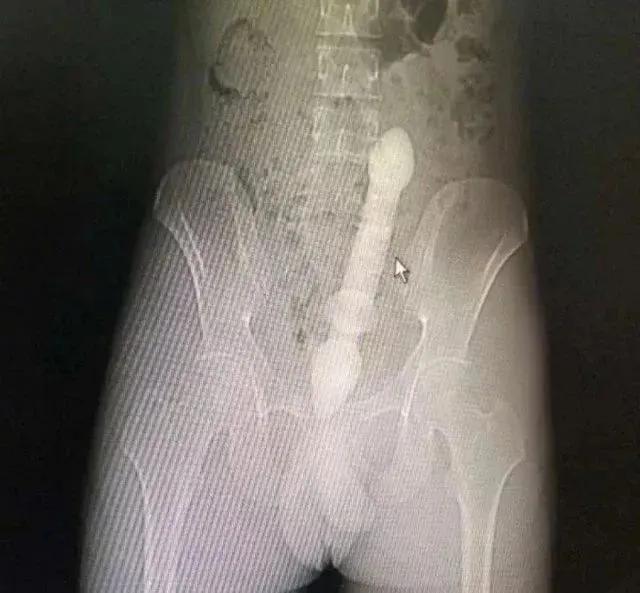

一位50多岁的男子发现了这种新奇玩法,把重达10斤的哑铃塞进了肛门。

医生会通过一系列检查如直肠指诊、X线来确定体内的异物是什么,在什么位置,这一点非常关键,因为只有搞清楚里面的真实情况,医生才能找到合适的方法把异物取出。